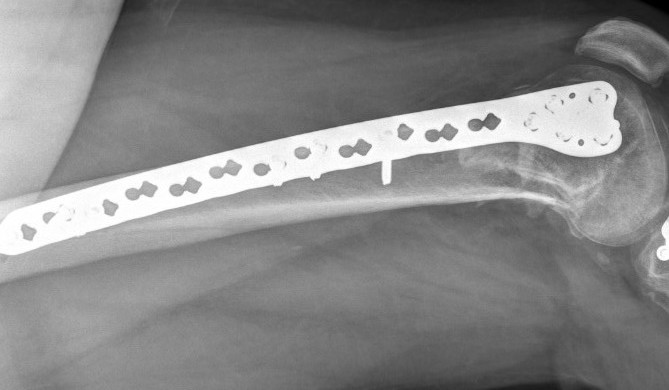

Plate + Nail

Dual Plate

Plate + Retrograde nail

Indications

Significant comminution

Loss of medial cortical buttress